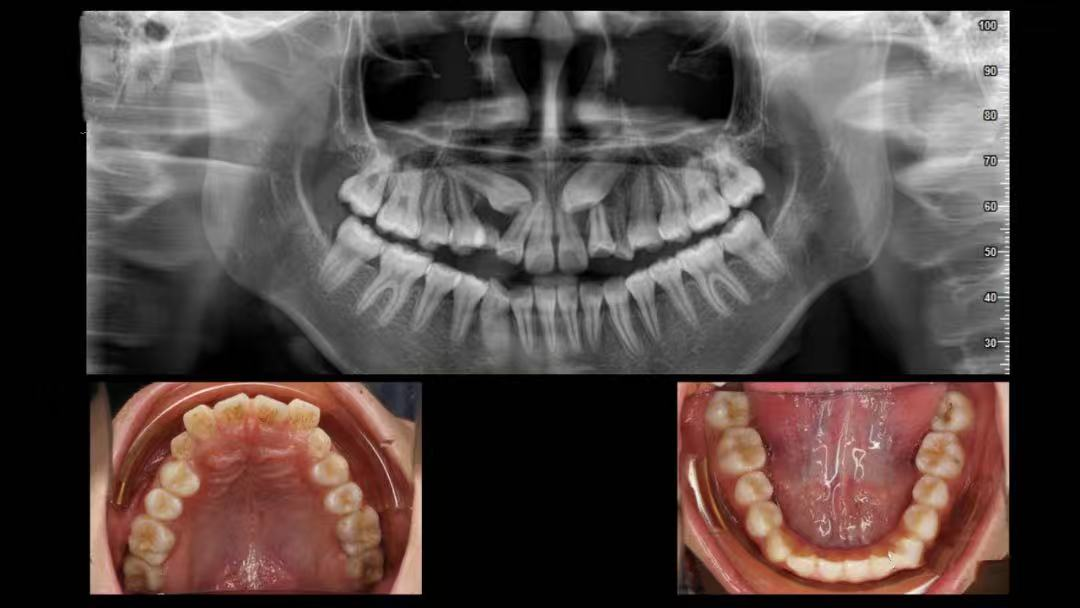

简单来说,埋伏牙就是牙齿在萌出的过程中,因为各种原因没能顺利长到口腔里,而是 “藏” 在了颌骨里面。这就好比一颗种子被种下去后,却始终没有破土而出,默默待在土壤里一样。

值得庆幸的是,随着多学科联合治疗的开展以及正畸技术的不断发展与完善,更多的上颌前牙埋伏阻生齿得以矫治和保留。通过正畸 - 外科联合牵引助萌复杂埋伏阻生牙的方法,往往能获得良好的效果,帮助患儿健康自信地成长。

如果大家怀疑自己有埋伏牙,一定要及时去正规的口腔医院进行检查。通常情况下,拍个 X 光片就能清楚地看到牙齿的情况了。